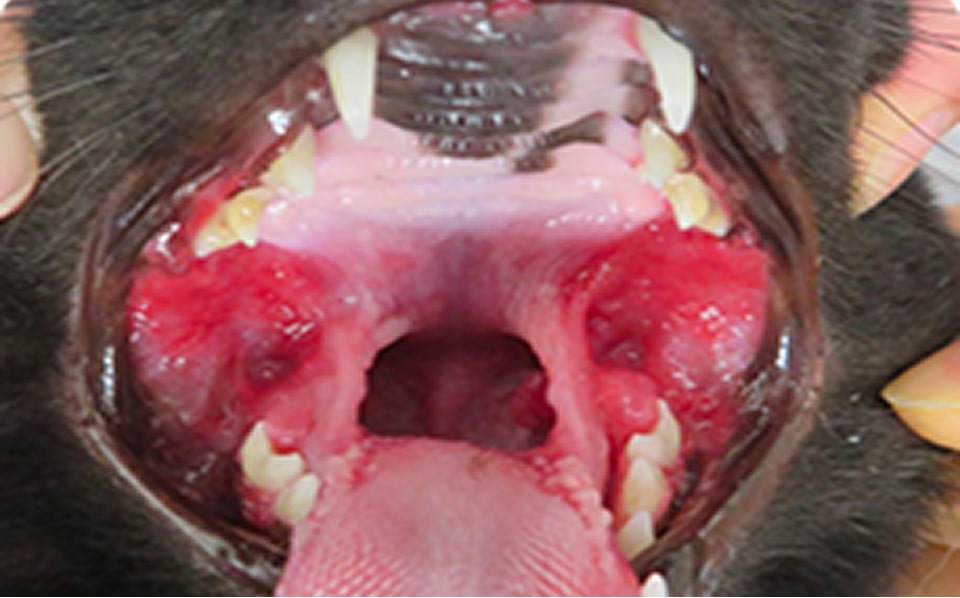

口腔内の歯肉や、口腔の尾側粘膜に腫脹や潰瘍が見られます。

症例

歯肉口内炎